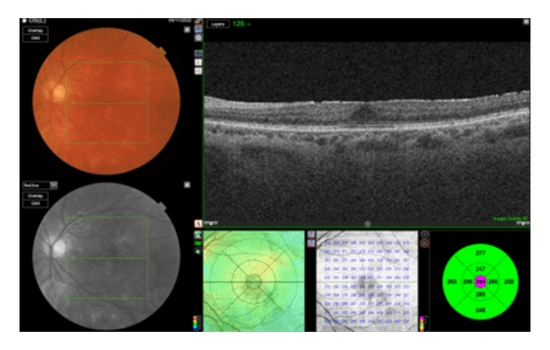

A 62-year-old patient sought a second opinion following a diagnosis of intraocular inflammation in both eyes, which was more severe in the right (BCVA: 0.4 LogMAR) than the left (BCVA: 0.3 LogMAR). An optician diagnosed vitritis. A month later, a local hospital diagnosed the patient with birdshot chorioretinopathy and initiated treatment that included Ozurdex intravitreal therapy in both eyes, oral prednisolone, and methotrexate.

Fundus Color (OS)

OCT (OS)

Fluorescein Angiography (OS)